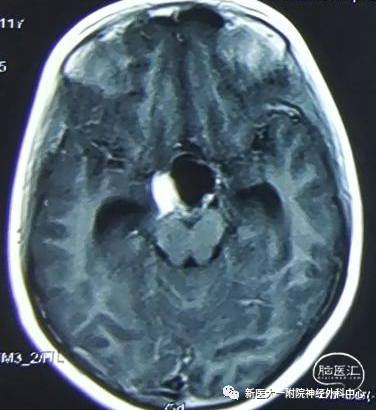

术前头颅MRI

MRI提示:鞍区可见一类圆形囊实性占位灶,病灶内见短T1长T2囊性区及等T1短T2实性区,增强扫描病灶内实性部分不均匀强化。